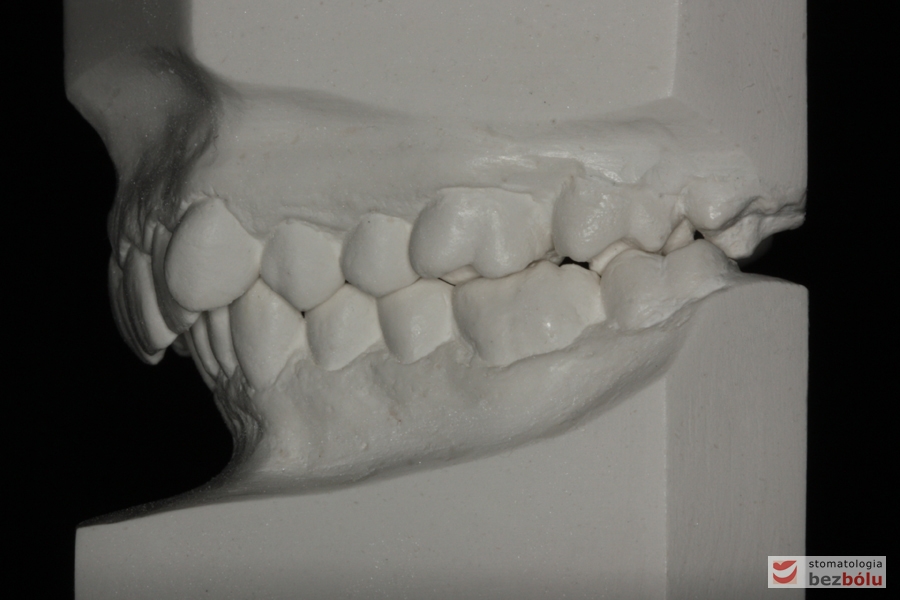

Pacjentka lat 26 zgłosiła się do gabinetu celem korekcji uśmiechu. Głównym zmartwieniem były problemy estetyczne, które znacznie wpływały na jakość życia pacjentki. Wykonano leczenie zachowawcze zębów oraz analizę cefalometryczną i analizę modeli diagnostycznych. Zaplanowano leczenie aktywne aparatem DAMON dla szczęki i żuchwy, które trwało 2 lata. Po fazie leczenia aktywnego rozpoczęto leczenie retencyjne z użyciem szyny tłoczonej dla szczęki i retainera stałego dla żuchwy.